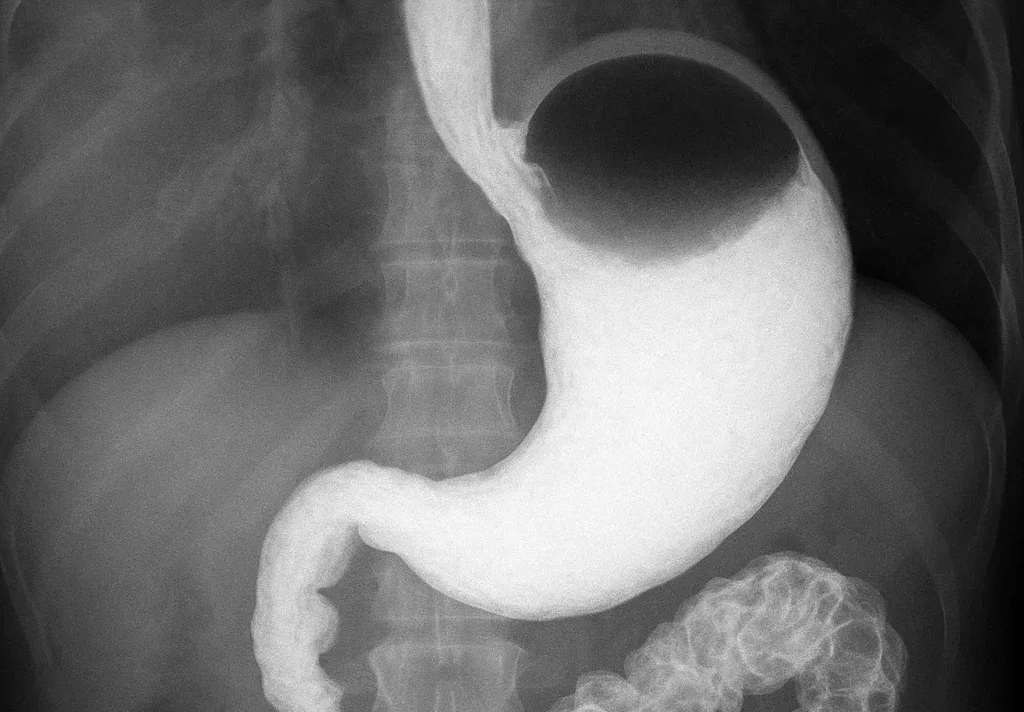

Для проведення рентгеноскопії у шлунок пацієнта перорально вводиться контрастна речовина (спеціальна суспензія барію), яка покриває стінки органа, що дозволяє лікареві у реальному часі оцінити усі можливі зміни досліджуваної зони.

Далі пацієнт розташовується перед рентген-апаратом в положенні стоячи або лежачи, а лікар проводить серію знімків під різними кутами та оцінює цілісність шлунка, його розмір і функціональність. Проходження контрастної речовини по шлунково-кишковому тракту, виділяє його на фоні інших органів і дозволяє зафіксувати усі зміни, як на екрані монітора, так і на знімку.

Рентген шлунка та стравоходу з барієм дозволяє побачити:

- гастрити;

- виразки шлунка;

- поліпи шлунка;

- рак шлунка (рентген показує тільки наявність пухлини);

- порушення моторики шлунка;

- стриктури або закупорки;

- ГЕРХ (рефлюксна хвороба);

- недостатність/кили сфінктерів стравоходу та/або шлунка тощо.